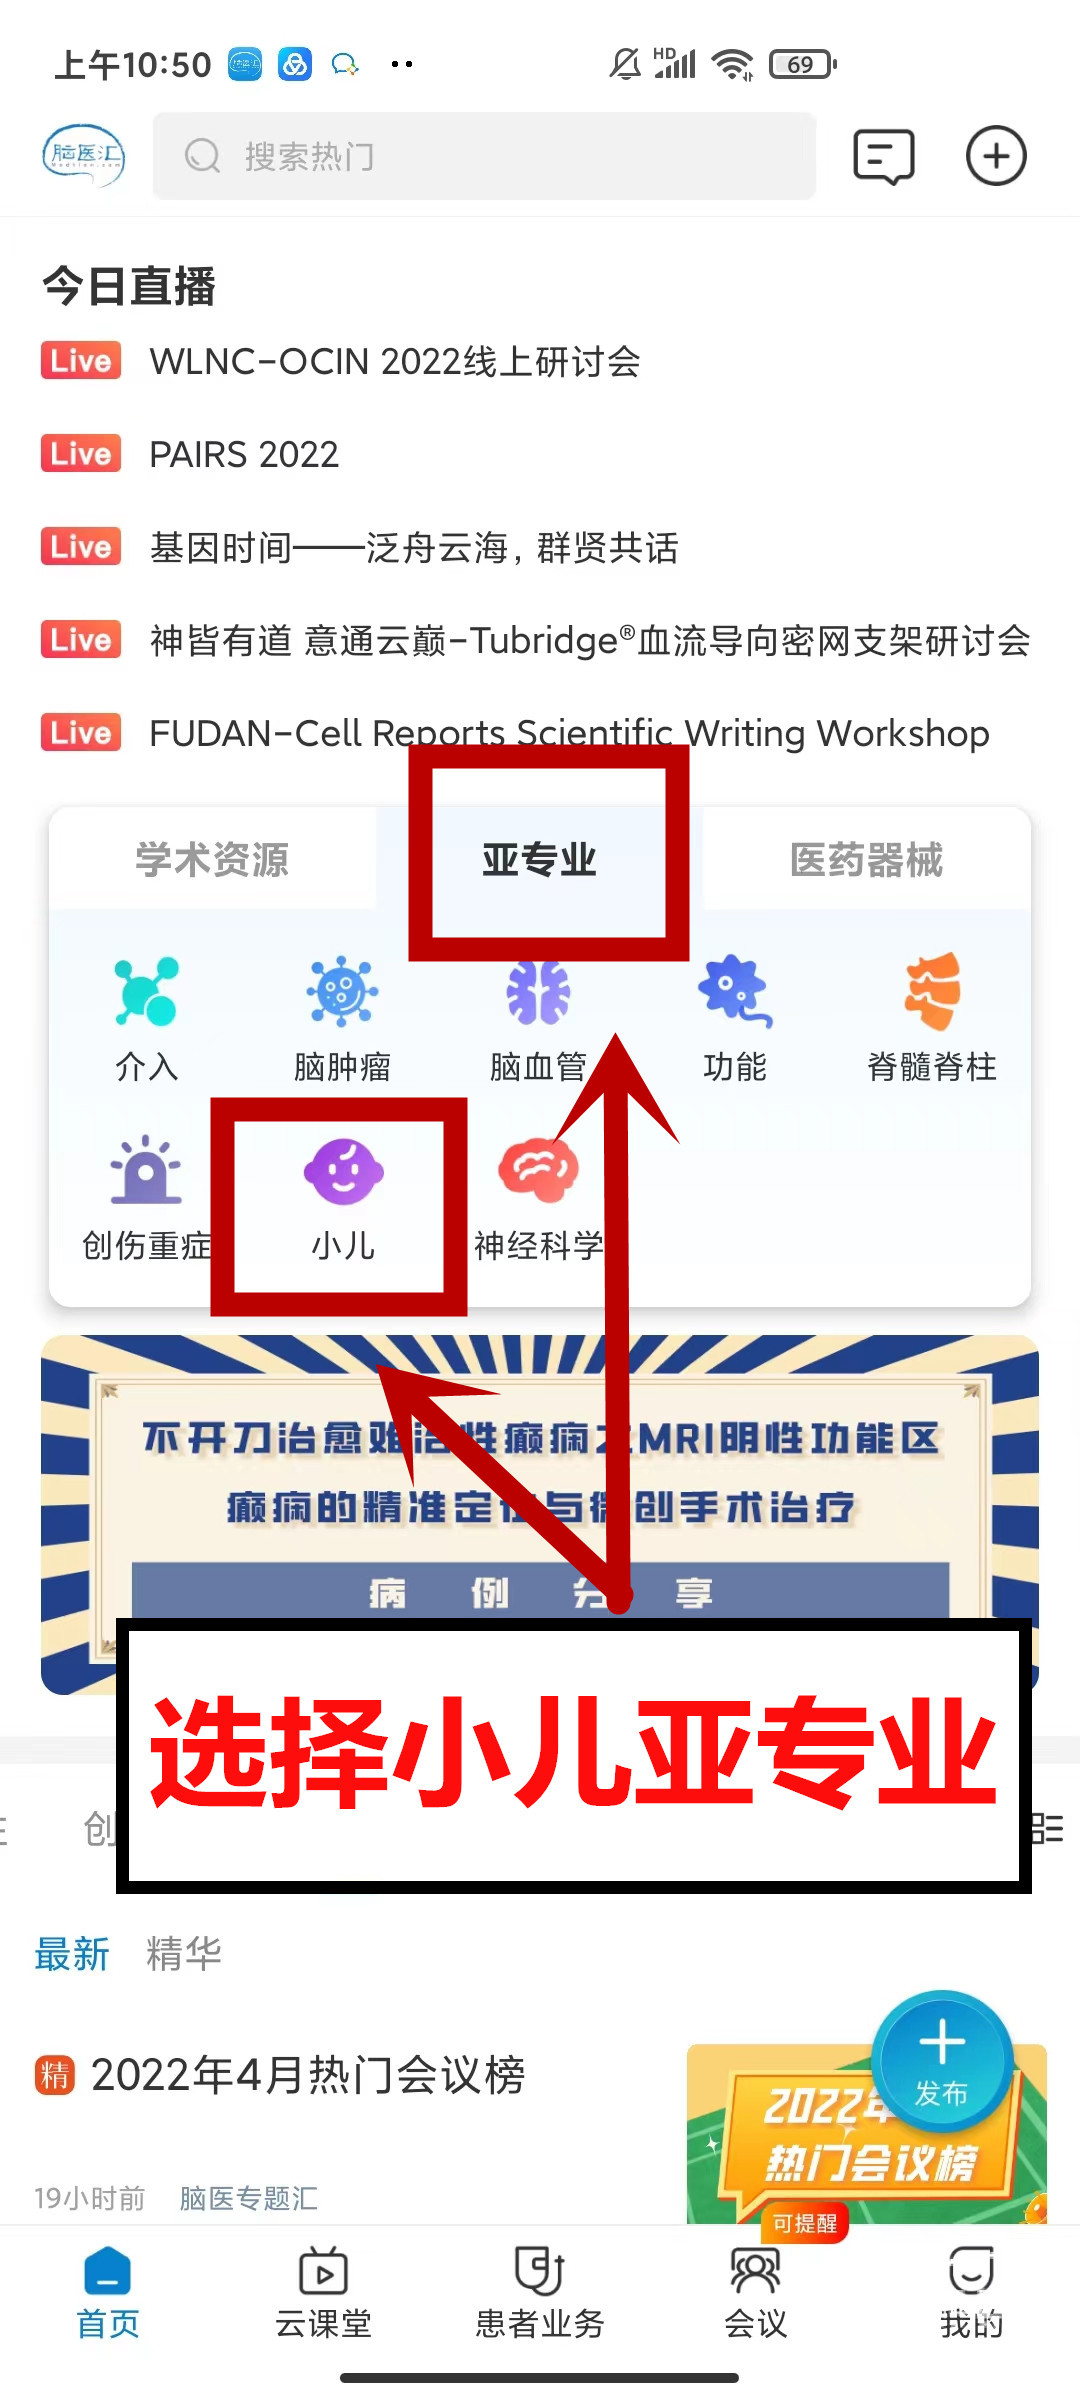

TIPS!

关注更多#小儿神外#领域精彩内容,就锁定“小儿”频道吧!

或者